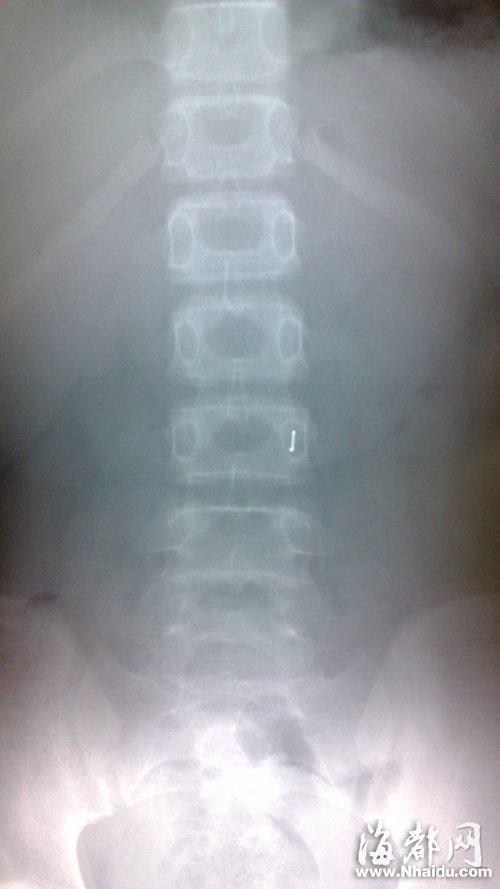

X光片显示女生肚子里有金属异物(画圈处)

值班医生初步检查三名女生的症状后,安排她们做X光检查。从X光片可看出,她们腹内均存在椭圆状金属异物,且分布在肠子的不同部位。估计是玩具胶囊内含有金属异物,通过食道,滑落到胃里,又下行滑到了肠子。